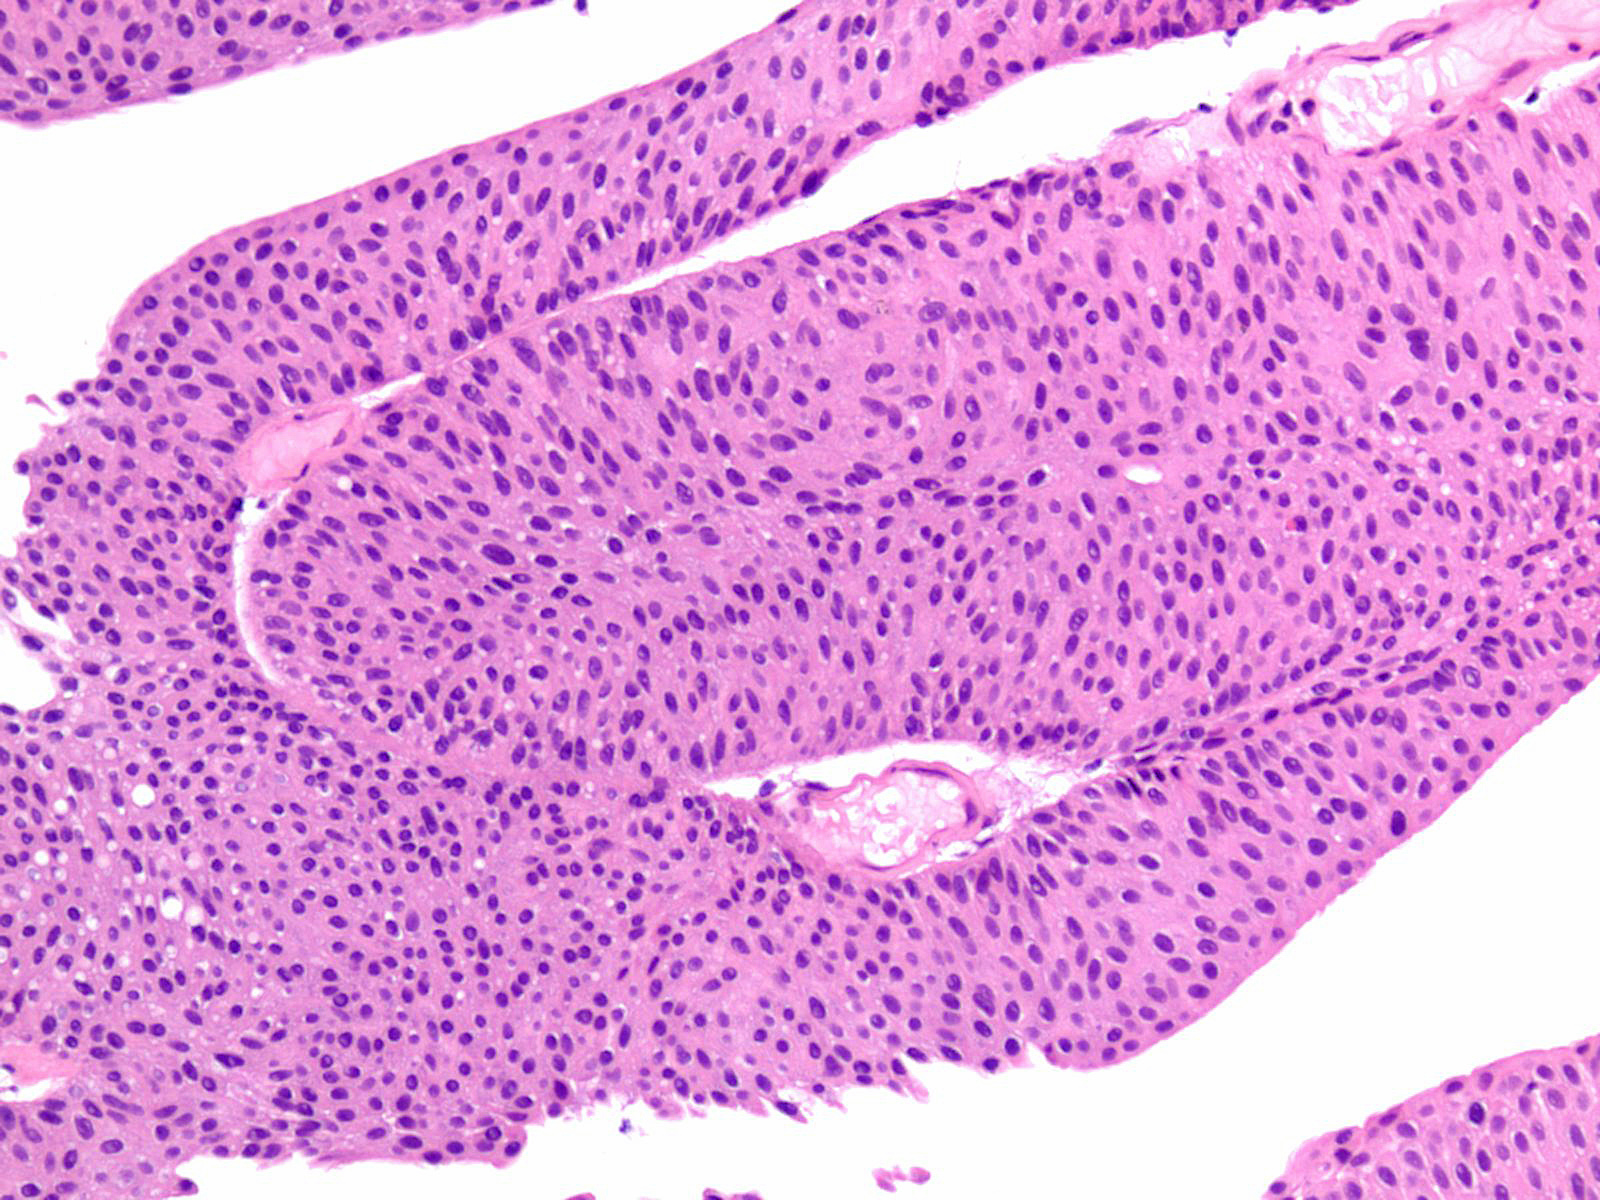

Consensus grade: Low-grade papillary urothelial carcinoma (LG-PUC)

Case description (by case creator):

Lesion shows moderate variation in nuclear size, shape and chromatin. Scattered nuclei are significantly enlarged and hyperchromatic relative to other nuclei. Lesion still maintains an overall orderly appearance.